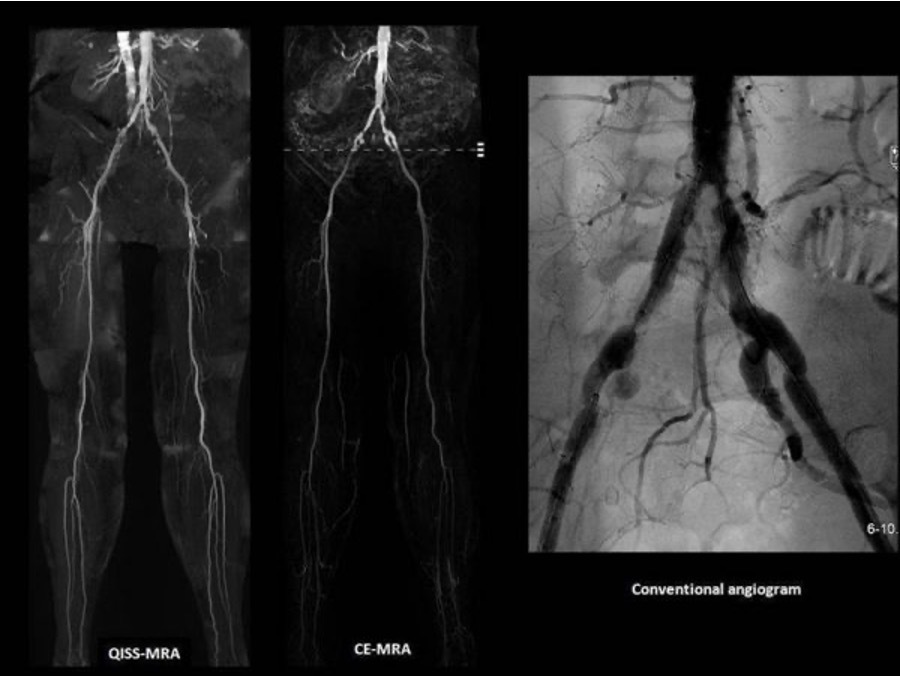

What is an angiogram?

Medical imaging technique used to visualise the inside, or lumen, of blood vessels and organs of the body, with particular interest in the arteries, veins, and the heart chambers.

Can also get CT angiogram and becomes coloured